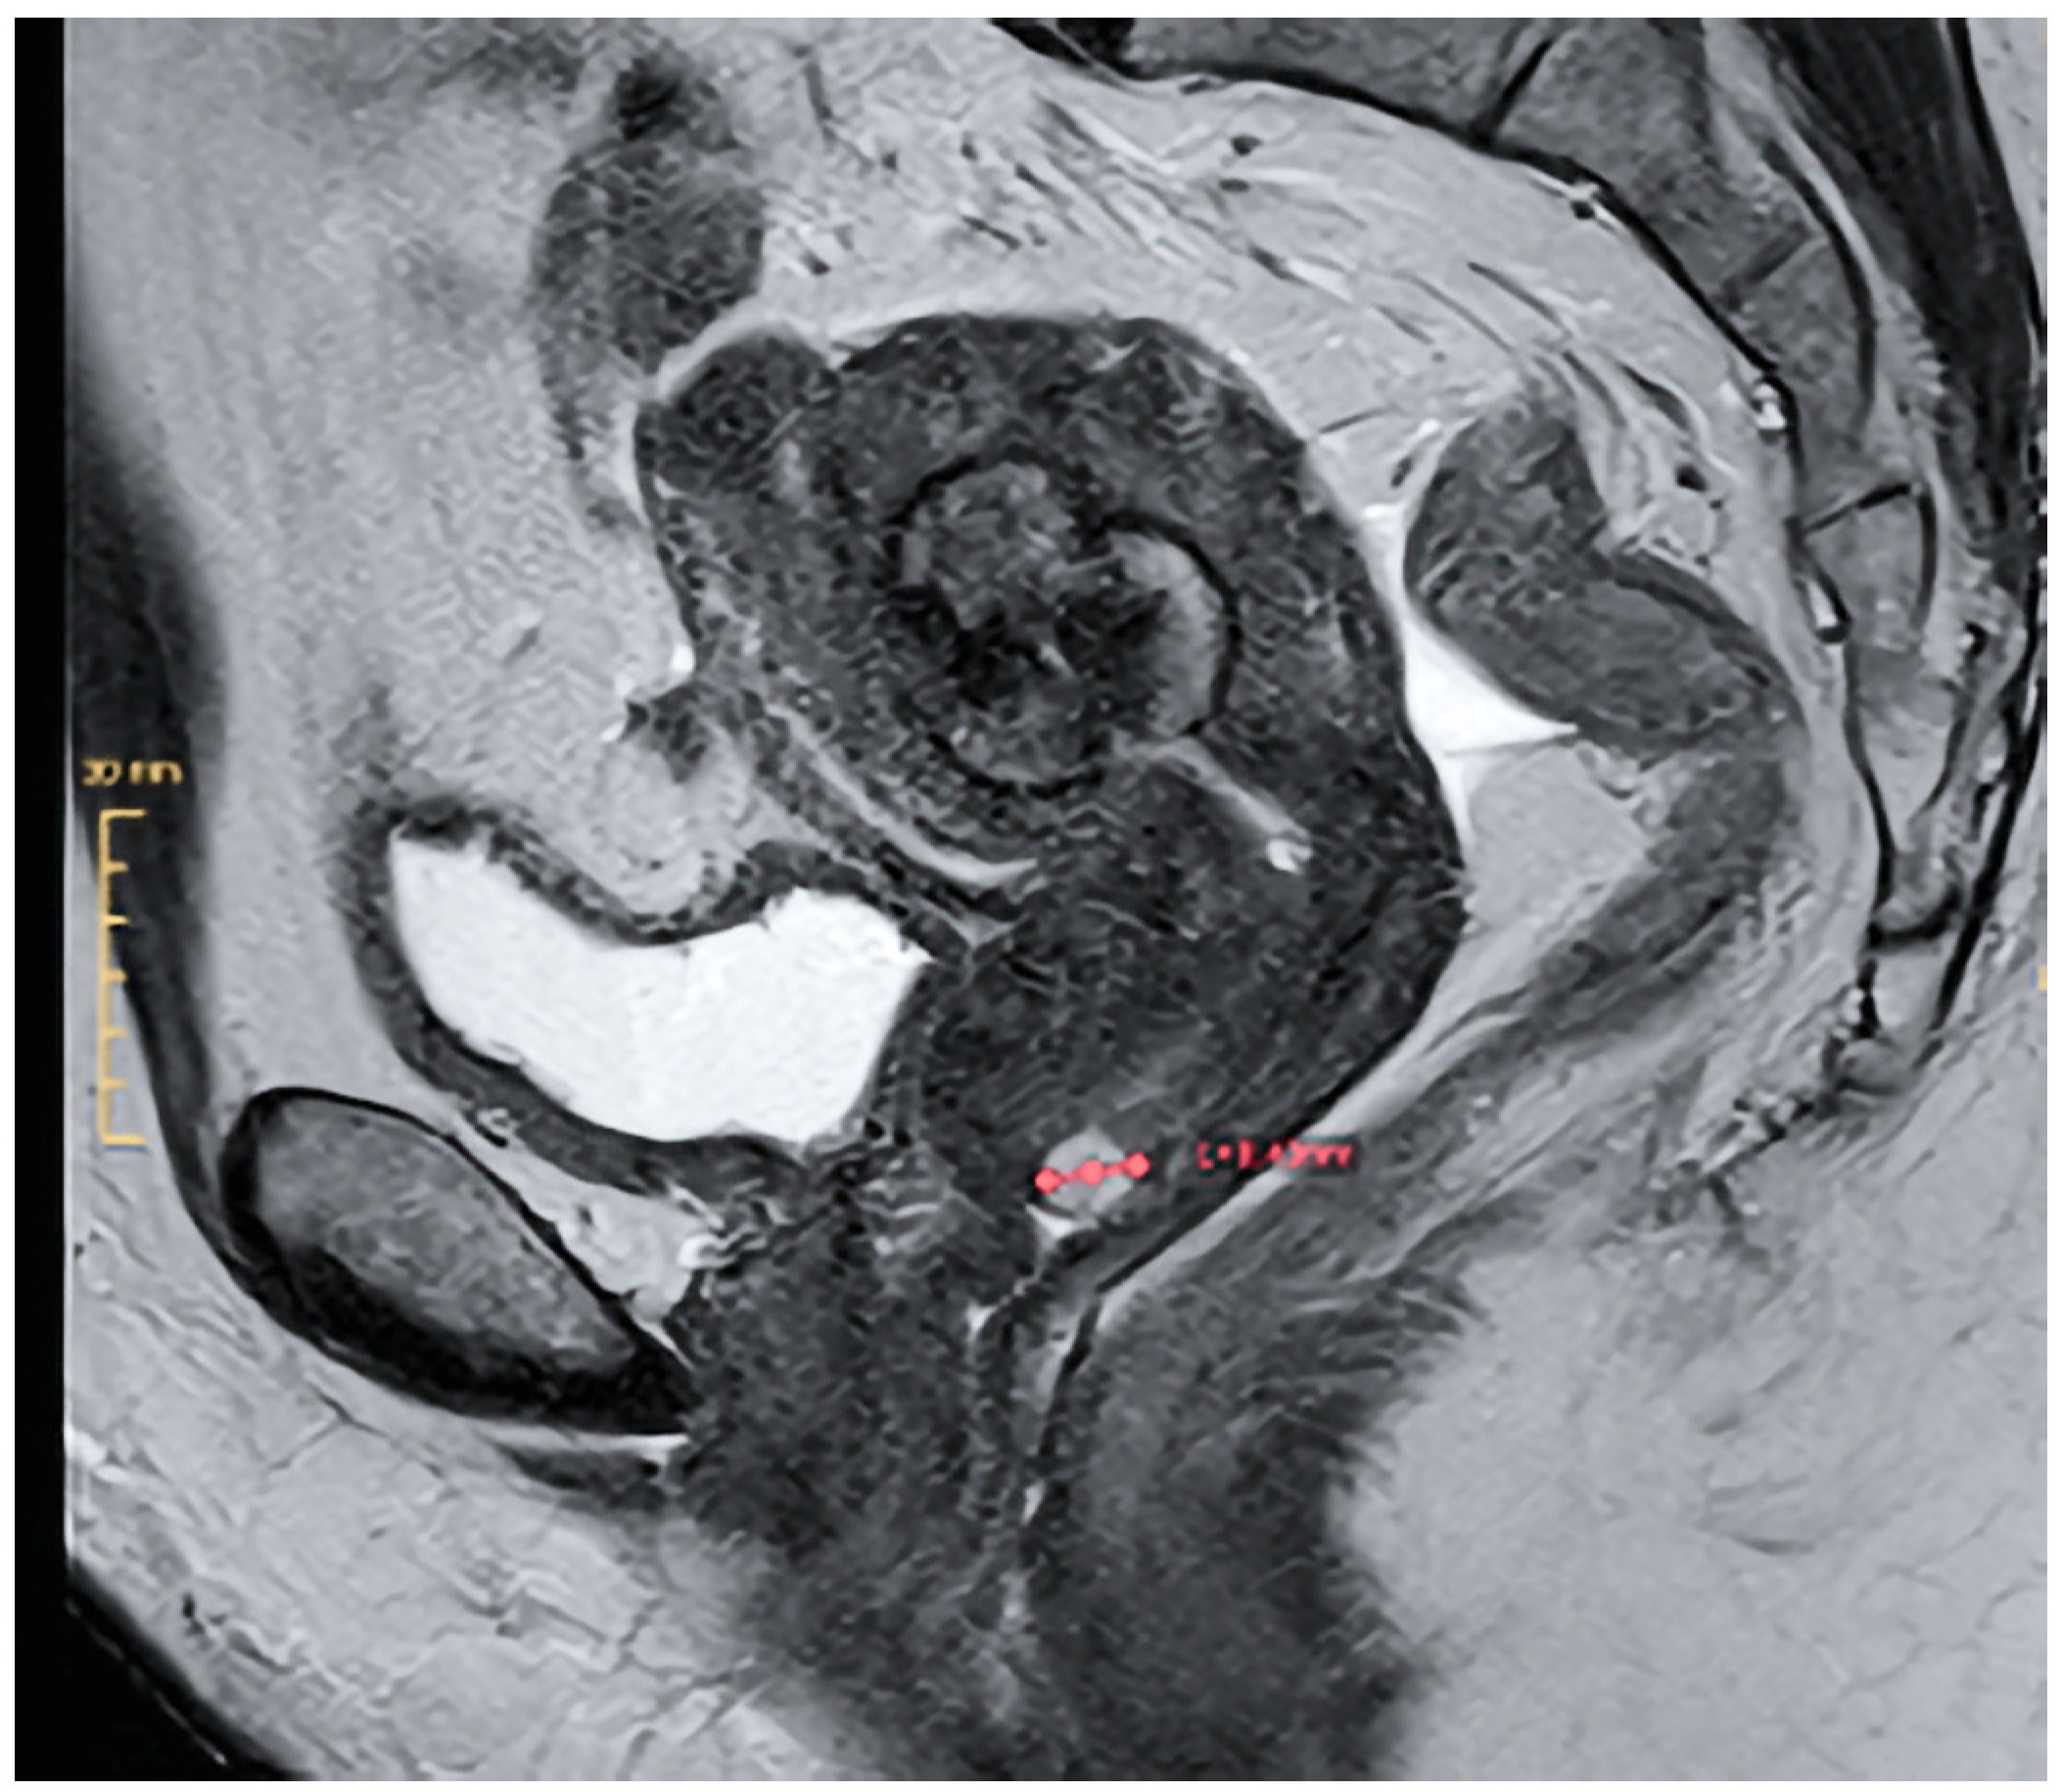

Three weeks postoperatively, the patient experienced a vaginal expulsion of an approximately 2.5 cm diameter mass. The patient preserved the tissue, permitting histopathologic examination, confirming the hysteroscopic biopsy diagnosis of a STUMP. Magnetic resonance imaging (MR) of the pelvis revealed a 3.1 cm residual mass in the endometrial cavity without signs of myometrial invasion, along with a 0.7 cm calcified intramural fibroid. There was no sign of lymphadenopathy (Figure 4).

Figure 4. T2-weighted MR image demonstrating a 3.1 cm type 2 myoma and a small Nabothian cyst in the uterine cervix.